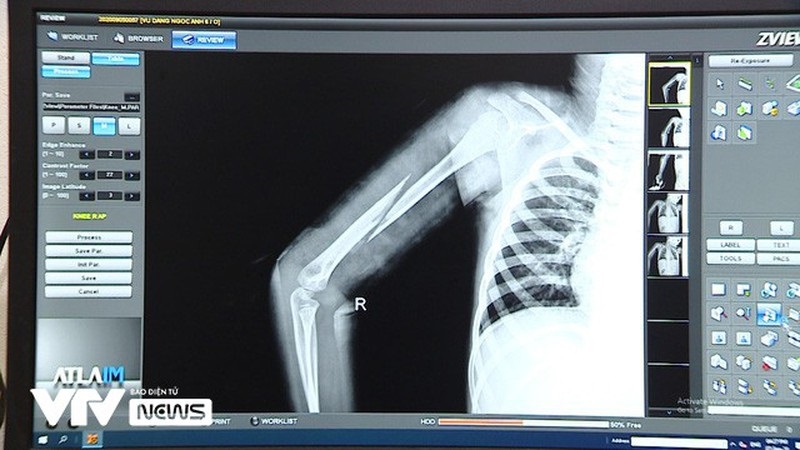

Theo nguồn tin của báo Pháp luật Việt Nam, sau khi nhận được tin báo của bà Hương (mẹ Kiên), cơ quan chức năng đã tiến hành giải cứu cháu Ngọc Anh rồi đưa đến Trung tâm y tế thị xã Từ Sơn điều trị vết thương. Các bác sĩ khám sơ bộ phát hiện người cháu Ngọc Anh có nhiều vết bầm, tụ máu ở phần gáy, lưng và đùi... Qua chụp x-quang tại Trung tâm Y tế thị xã Từ Sơn thì thấy cánh tay phải của cháu bị gãy lìa xương.

Bác sĩ Nguyễn Văn Đức - Phó Khoa ngoại tổng hợp (Trung tâm y tế thị xã Từ Sơn) cho biết, cháu Ngọc Anh nhập viện trong tình trạng hoảng sợ sau khi trải qua một sang chấn tâm lý nặng nề. Hiện các bác sĩ đã bó bột vết xương gãy, sau 1 tuần sẽ chụp x-quang lại xem xương có di lệch hay không.

Hình ảnh chụp cánh tay bị gãy của cháu Ngọc Anh (ảnh VTV News)